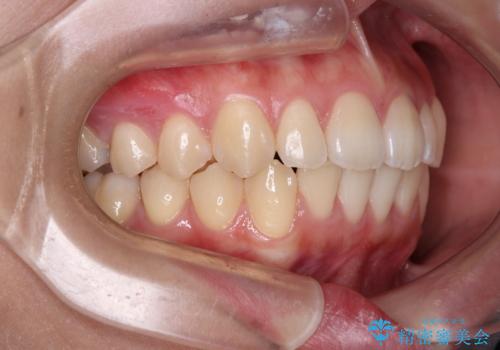

- デコボコを気にして来院された患者様です。

インビザラインでもワイヤー装置でも対応可能でしたが、自己管理の煩わしさの観点から、楽して治療のできるワイヤー装置を選択されました。

抜歯するほどではないものの、やや口元の突出感が気になっていたので、補助装置により上顎臼歯を後方に移動させることで、突出感改善を図ることとしました。